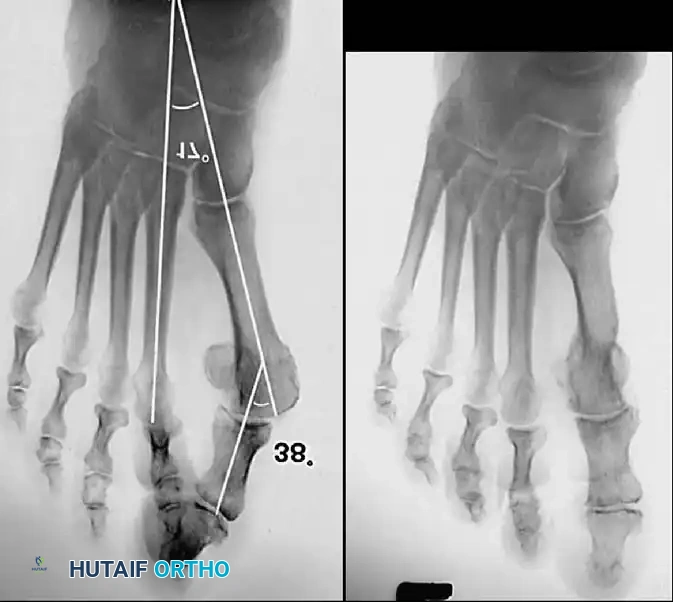

Hallux valgus (lateral deviation of the great toe) is not a single disorder, as the name implies, but a complex deformity of the fi rst ray that frequently is accompanied by deformity and symptoms in the lesser toes (Fig. 78-1). Often the angle between the fi rst and second metatarsals is more than the 8 to 9 degrees usually considered to be the upper limits of normal. The valgus angle of the fi rst metatarsophalangeal joint also is more than the 15 to 20 degrees considered to be the upper limits of normal (Fig. 78-2). If the valgus angle of the fi rst metatarsophalangeal joint exceeds 30 to 35 degrees, pronation of the great toe usually results. With this abnormal rotation, the abductor hallucis, which is normally plantar to the fl exion-extension axis of the fi rst metatarsophalangeal joint, moves further plantarward (Fig. 78-3). In this case, the only restraining medial structure is the medial capsular ligament with its capsulosesamoid portion (inserting into the base of the proximal phalanx) (Fig. 78-4) and capsulophalangeal portion (inserting into the plantar plate). The adductor hallucis, which is unopposed by the abductor hallucis, pulls the great toe further into valgus, stretching the medial capsular ligament (particularly the capsulosesamoid), attenuating this structure, and allowing the metatarsal head to drift medially from the sesamoids. In addition, the fl exor hallucis brevis, fl exor hallucis longus, adductor hallucis, and extensor hallucis longus increase the valgus moment at the metatarsophalangeal joint, further deforming the fi rst ray. The deep transverse intermetatarsal ligament runs between the plantar plates at the metatarsophalangeal joints and does not insert into bone on the adjacent sides of the metatarsal heads. Finally, the sesamoid ridge on the plantar surface of the fi rst metatarsal head (the crista) fl attens because of pressure (abutment) from the tibial sesamoid (Fig. 78-5). With this restraint lost, the fi bular sesamoid displaces partially or completely into the fi rst intermetatarsal space (see Fig. 78-2). In this situation, the patient is bearing less weight on the fi rst ray and more on the lesser metatarsal heads, increasing the likelihood of transfer metatarsalgia, callosities, and stress fracture of a lesser metatarsal.

Inadequate vascularity or sensibility should be investigated thoroughly before bunion surgery is considered. In addition, the position of the articular surface of the metatarsal head in relation to the longitudinal axis of the fi rst metatarsal should be determined (Fig. 78-8). Standard preoperative radiographs should include standing dorsoplantar and lateral views, a nonstanding lateral oblique view, and axial sesamoid views (Fig. 78-9). The hallux valgus angle and the fi rst-second intermetatarsal angle should fi rst be drawn on the standing dorsoplantar view by bisecting the shafts of the bones (Fig. 78-10), with an awareness of the normal ranges. These angles are most frequently cited as guidelines for treatment decisions, but Donnelly et al. reported that interobserver measurements of the hallux valgus angle varied by approximately 6 degrees and of the intermetatarsal angle by 4 degrees. They cautioned that potential errors in measurement should be considered when these parameters are used to make treatment decisions. The hallux valgus interphalangeus angle and any evidence of degenerative arthritic changes at the fi rst metatarsophalangeal or metatarsocuneiform joints should be documented. Oddities may be present and, if overlooked, may compromise a technically well-done procedure. Mann emphasized that the presence of an os inter-

(center of the proximal diaphysis) as reference points. They found that measured correction of the hallux valgus and intermetatarsal angles varied by approximately 9 degrees depending on which reference points were used. Recommendations of Coughlin, Saltzman, and Nunley (American Orthopaedic Foot and Ankle Society Ad Hoc Committee on Angular Measurements) included standardized radiographic technique, specifi c placement of reference points (Fig. 78-11), use of a protractor rather than a goniometer for measurements, and, after distal osteotomies, dual measurements using a center-head technique and a Mose sphere.

Fig. 78-10 Method of measuring hallux valgus angle and intermetatarsal angle. Center points are connected, and intersecting lines defi ne angles.

Keller Resection Arthroplasty The Keller procedure combines resection hemiarthroplasty of the fi rst metatarsophalangeal joint with removal of the medial eminence of the fi rst metatarsal (Fig. 78-28). Although removing the base of the proximal phalanx decompresses the joint and mobilizes the hallux, allowing marked correction of valgus, the varus of the fi rst metatarsal is not corrected, and maintaining correction of the valgus of the hallux is diffi cult. Other complications of the Keller procedure have been emphasized in the literature to such an extent (with neither the incidence nor the severity of such complications clearly documented) that the indications for this procedure have been limited severely. In our experience, however, complications are uncommon if patients are selected carefully. Modifi cations in the original technique also have allowed expansion of the indications for the Keller bunionectomy. Candidates for the Keller procedure are patients older than 50 years with moderate-to-severe hallux valgus (30 to 45 degrees); intermetatarsal angles of 13 degrees or less, indicating mild-to-moderate metatarsus primus varus; and pain over the medial eminence with any shoe worn, so the variety of shoes the patient can wear is severely limited. An incongruous fi rst metatarsophalangeal joint caused by

Fig. 78-26 Modifi ed McBride bunionectomy (DuVries; Mann). A, Medial capsule of second metatarsophalangeal joint is sutured to lateral capsule of fi rst metatarsophalangeal joint with interposition of released adductor hallucis. B, Medial capsular resection. C, Confi guration after capsular resection. D, After capsular imbrication, hallux should rest in neutral position or not exceed 5 degrees of varus. E, Postoperative dressing technique (Mann). ( E after Beverly Kessler; courtesy of LTI Medica and The Upjohn Company.) lateral subluxation of the phalanx on the metatarsal head, severe lateral displacement of the sesamoids, and any evidence of degenerative cartilage changes in the joint all are radiographic indications for the Keller procedure. Two modifi cations in technique can expand these indications, however, to include patients with more severe deformities (Fig. 78-29) (but not to include younger patients): fi bular sesamoidectomy and lateral displacement of the fi rst metatarsal. Using these modifi cations, Donley et al. obtained an average 18-degree correction of the metatarsophalangeal angle and an average 6-degree correction of the intermetatarsal angle in 38 patients (50 feet);

95% of patients were satisfi ed with their results. Patients with 50 degrees or more of valgus of the hallux (18 to 20 degrees of varus of the fi rst metatarsal), complete lateral dislocation of the sesamoids, marked degenerative changes, and severe pronation of the hallux may benefi t functionally and cosmetically from alterations of the standard technique.

Fig. 78-29 Severe hallux valgus with bursa formation in 70-year-old woman. A and B, Anteroposterior and lateral clinical photographs of patient’s right foot. C, Correction of deformity by modifi ed Keller procedure. D, Preoperative and postoperative weight bearing radiographs of same patient.